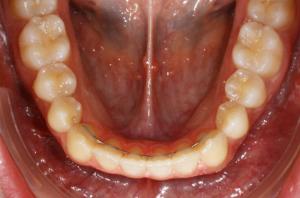

Cette phase est aussi importante que le traitement lui-même.

De façon pratique, des fils métalliques très fins sont collés à l’arrière des dents antérieures en haut et en bas. Ils ne sont ni visibles, ni gênants. Leur rôle est de conserver l’alignement des dents à la fin du traitement orthodontique pendant la phase de stabilisation des tissus de soutien qui entourent la dent (os et gencive), puis au cours de la maturation physiologique (vieillissement).

La première année après la dépose de l’appareil, une gouttière de contention doit être portée sur les dents du haut d’abord toutes les nuits, puis le port est diminué jusqu’à être arrêté complètement au bout d’un an.

Cette période de contention dure en moyenne 1 à 2 ans et permet chez l’adolescent de surveiller l’évolution de ses dents de sagesse et le déroulement de la fin de sa croissance.